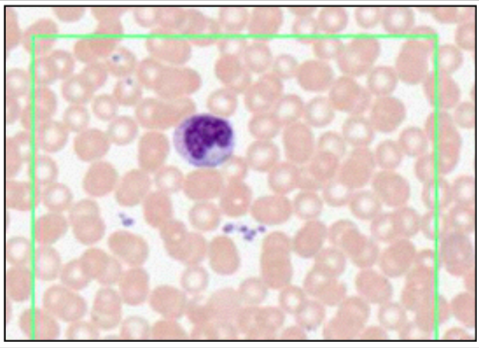

NEUTROPHILS - POLYMORPHONUCLEAR LEUKOCYTES (LEISHMAN’S STAIN)

- multi-lobar nucleus

- most numerous

- phagocytic

- engulf and destroy bacteria

- leave blood stream to enter tissue @ infection site

fine granules = GRANULOCYTES

- primary - lysosomes, acid hydrolases, antibac and digest

- secondary - neutrophil specific, regulation of inflammation response

- tertiary - facilitate insertion of proteis to cell membrane

lobes = 2-4, number increases with age